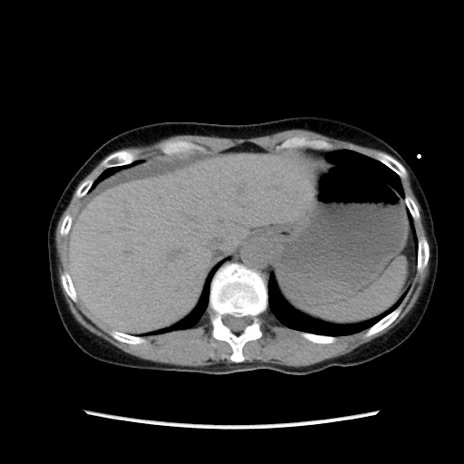

症例32(横断像)

【症例】40歳代 女性

【主訴】上腹部痛、嘔気・嘔吐

【現病歴】約9時間前頃から急に上腹部痛、嘔気、嘔吐が出現。改善しないため救急要請。

【既往歴】子宮頚癌(広汎子宮全摘術、放射線療法)、腸閉塞

【身体所見】腹部:平坦、軟、腸雑音亢進、上腹部を中心に腹部全体に圧痛あり。

【データ】WBC 8400、CRP 0.03